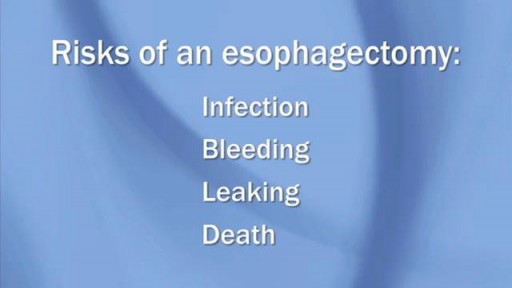

Lung cancer is a type of cancer that begins in the lungs. Your lungs are two spongy organs in your chest that take in oxygen when you inhale and release carbon dioxide when you exhale. Lung cancer is the leading cause of cancer deaths in the United States, among both men and women. Lung cancer claims more lives each year than do colon, prostate, ovarian and breast cancers combined. People who smoke have the greatest risk of lung cancer. The risk of lung cancer increases with the length of time and number of cigarettes you've smoked. If you quit smoking, even after smoking for many years, you can significantly reduce your chances of developing lung cancer.